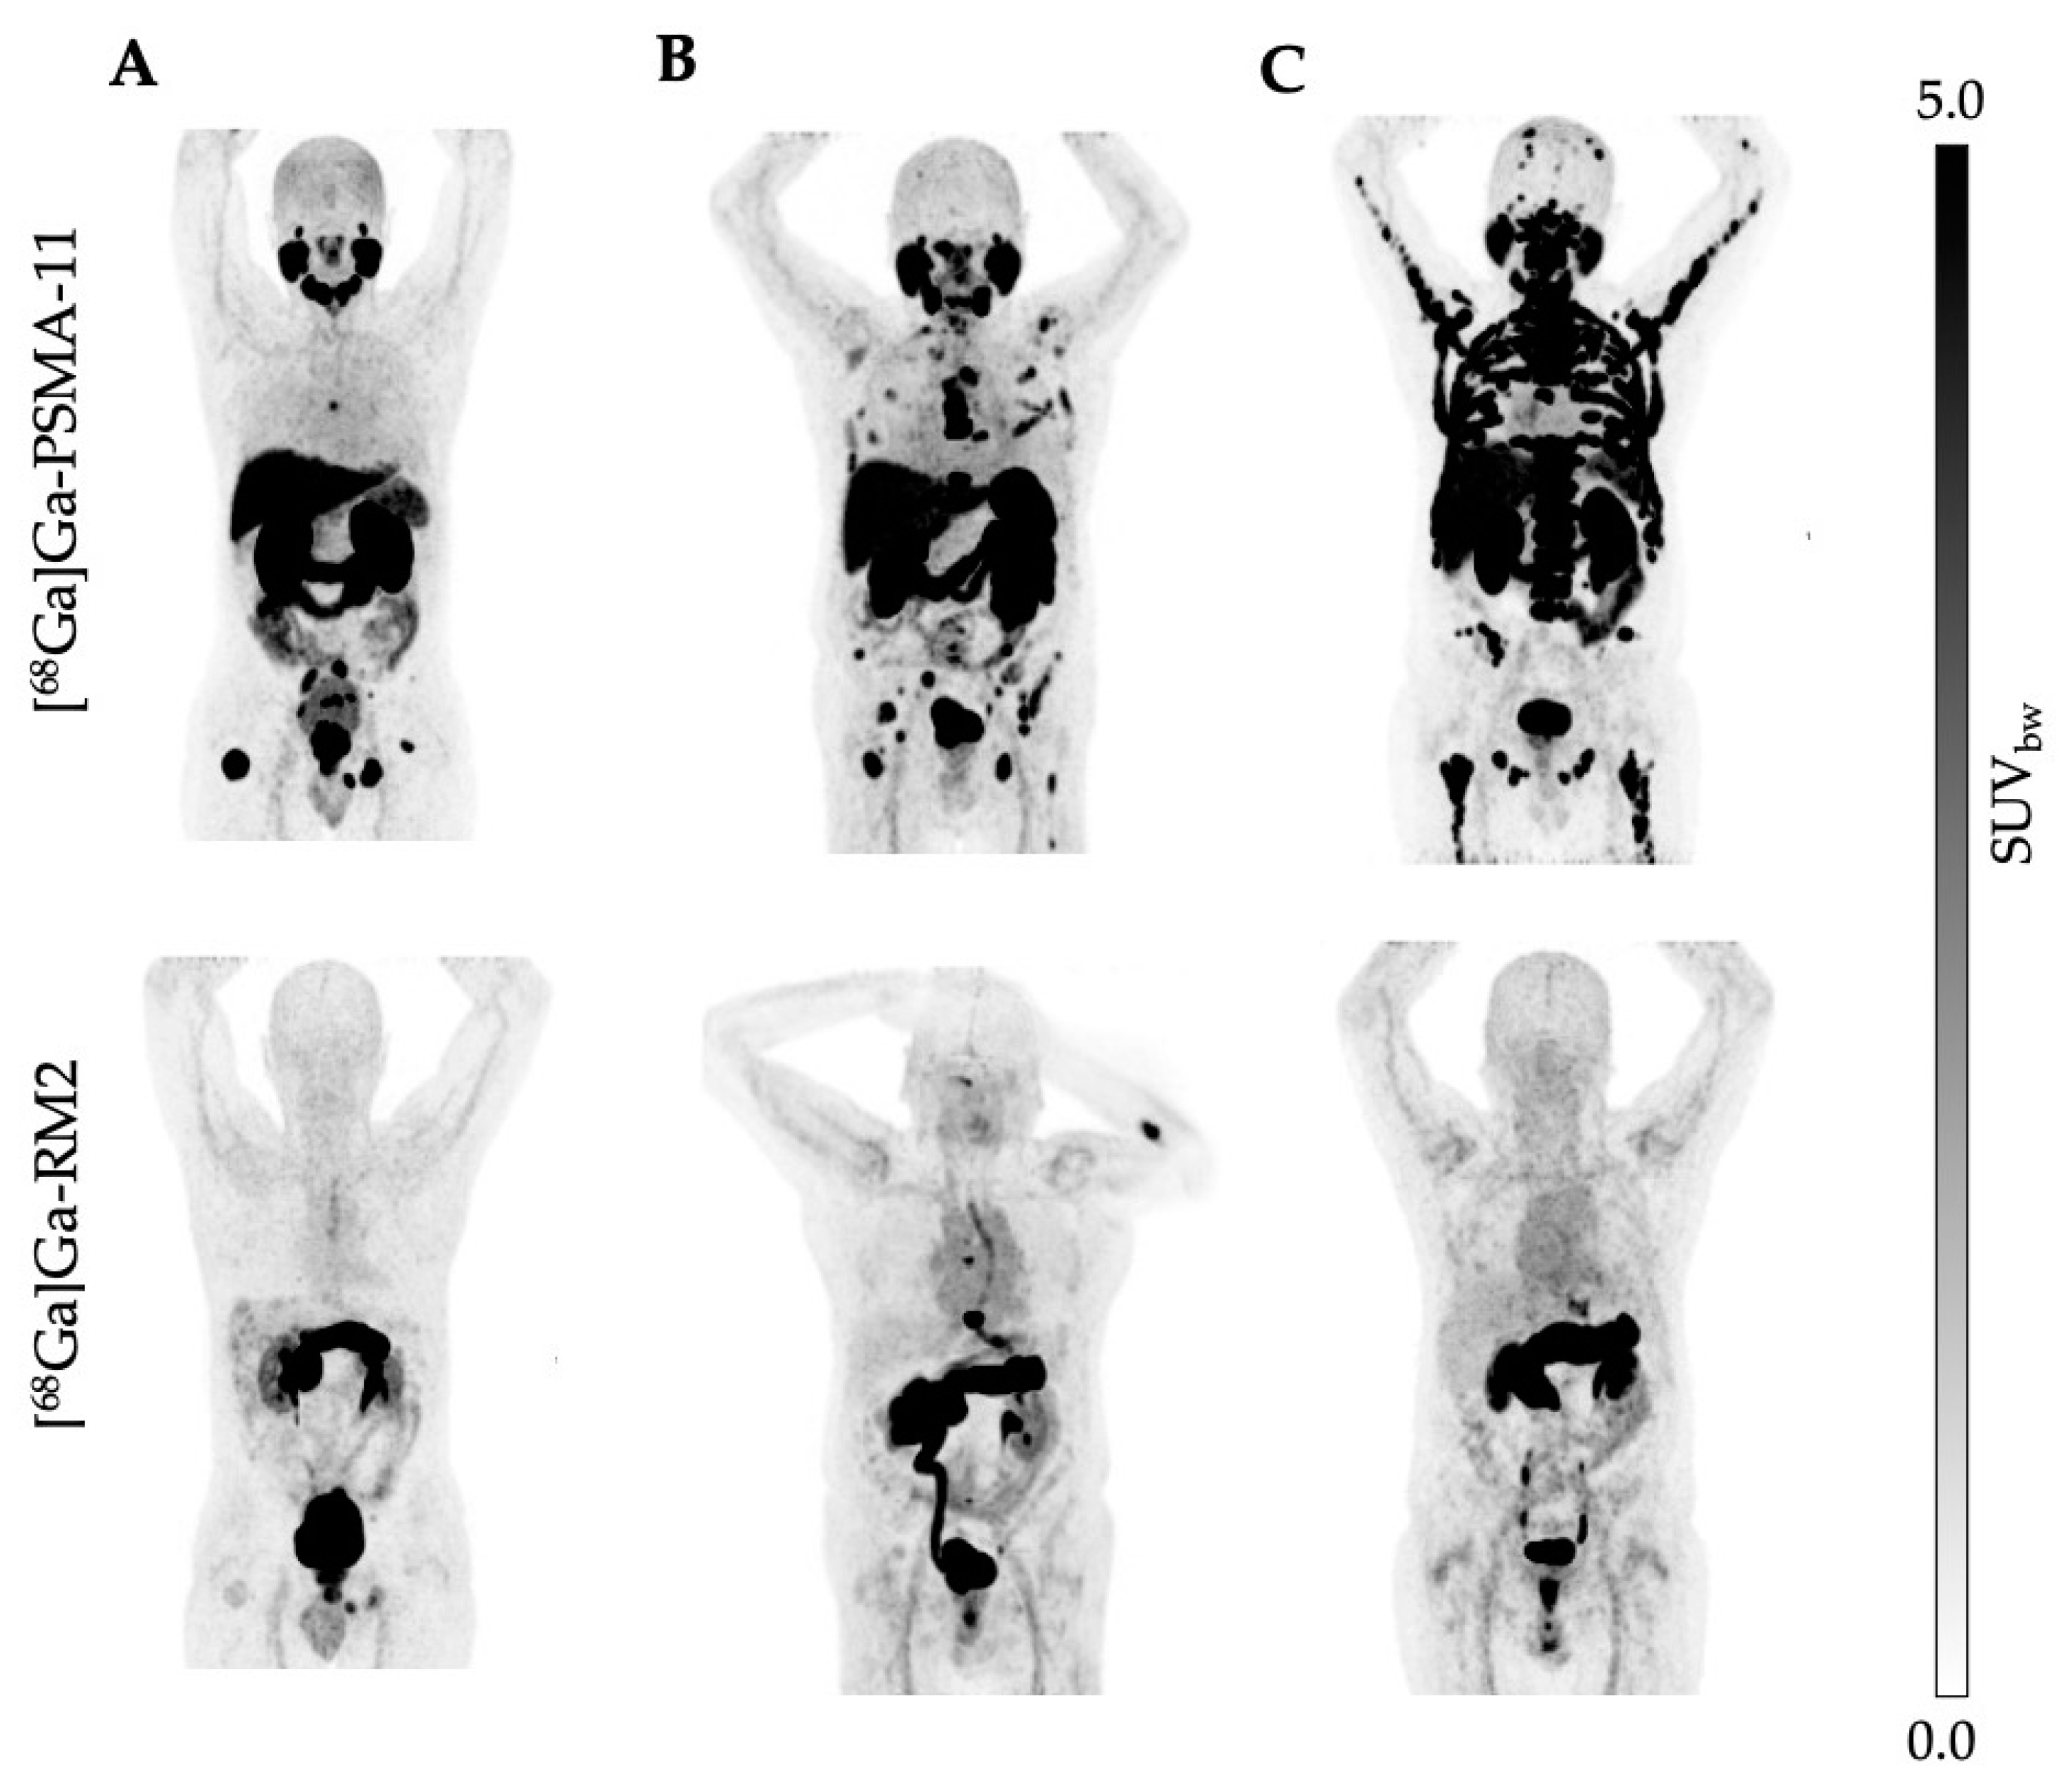

Figure 1.

(A–C) Maximum-intensity projections (MIP) of [68Ga]Ga-PSMA-11 (upper row) and [68Ga]Ga-RM2 (lower row) PET images of patients with similar biodistribution and tumor uptake (n = 14).

Figure 2.

(A–C) Maximum-intensity projections (MIP) of [68Ga]Ga-PSMA-11 (upper row) and [68Ga]Ga-RM2 (lower row) PET images of patients with high PSMA but low GRPr expression (n = 13).

The administration of [68Ga]Ga-PSMA-11, [68Ga]Ga-RM2, and the imaging procedure were well tolerated and no adverse events, discomfort, or change in vital signs was observed. The excretion profile of both tracers was similar with a predominant renal clearance via the kidneys observed for [68Ga]Ga-PSMA-11 and [68Ga]Ga-RM2 (Figure 1 and Figure 2). However, we observed differences in the physiological biodistribution between the two tracers in the submandibular, parotid, and lacrimal glands, liver, and small intestine, where unlike [68Ga]Ga-PSMA-11, [68Ga]Ga-RM2 showed no uptake. In contrast, [68Ga]Ga-RM2 showed high uptake in the pancreas, whereas no uptake of [68Ga]Ga-PSMA-11 was observed.

Specific uptake in tumor lesions in the prostate, lymph nodes, bone, and soft tissue was evident with both radioligands; however, the SUVmax values of [68Ga]Ga-PSMA-11 were statistically higher compared to [68Ga]Ga-RM2 in most lesions. Indeed, only 23.5% of the patients showed a high GRPr expression (Figure 1, Figure 2 and Figure 4).

Interestingly, in some patients with advanced disease, both tracers showed a similar biodistribution in tumor lesions (Figure 1). For those patients, alternating cycles between PSMA- and GRPr-targeted RLT may lead to the same treatment response but with less toxicity from each drug. The expression of PSMA in some healthy tissues, such as salivary and lacrimal glands, the kidney, and bone marrow, produces temporary side effects. Our studies, alongside others, have demonstrated that hematological side effects such as pancytopenia are transient and mainly limited to grade 2. Commonly, patients treated with PSMA-targeted RLT experience xerostomia, fatigue, and nausea [60]. In contrast, GRPr-targeted RLT does not affect salivary or lacrimal glands, and the first-in-human dosimetry study has reported that the treatment was well tolerated and showed no side effects. The most intensive uptake, however, is in the pancreas, which is considered a critical organ. Nonetheless, akin to other RLTs with Lutetium-177, the bone marrow is acknowledged as a critical organ, and no significant differences with PSMA-targeted therapies have been noted [26]. Nevertheless, for mCRPC the clinical benefit of using [177Lu]Lu-RM2 is limited to patients who have high expression of GRPr and experienced xerostomia as a dose-limiting event after PSMA-targeted RLT.